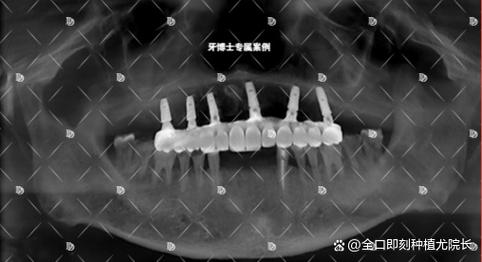

- 技术方案: 了解他们提供的种植方案(如即刻种植、微创种植、All-on-4等)是否先进、适合你。